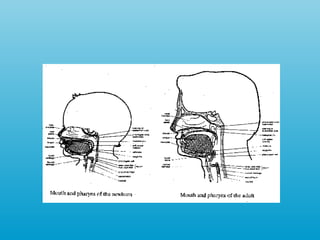

Respiración El centro que controla la respiración: bulbo raquideo. En el RN  ->  F aringe ejerce un rol fundamental.  La respiración del RN es rápida, abdominal, superficial y nasal , iniciando un patrón toráxico de respiración alrededor de los 3-4 meses.

Alimentación (RN a 3° mes) Suckling Acanalamiento de la lengua para el movimiento del bolo alimenticio en la parte posterior y ocurrencia de la deglucion. El reflejo de búsqueda  ->  importante para la    prontitud de la succion El bebe presentará periodos de succiones y pausas. El número de succiones por periodo puede variar La laringe  ->  elevada y más próxima a la base de    la lengua.

Alimentación (RN a 3° mes) La forma de protección más importante de las vías aéreas  ->  cierre completo y automático de la glotis durante la deglución. Bolsas de gordura en la región de las mejillas  ->  facilitan la succión

Respiración El centroque controla la respiración: bulbo raquideo. En el RN -> F aringe ejerce un rol fundamental. La respiración del RN es rápida, abdominal, superficial y nasal , iniciando un patrón toráxico de respiración alrededor de los 3-4 meses.

Alimentación (RN a3° mes) Suckling Acanalamiento de la lengua para el movimiento del bolo alimenticio en la parte posterior y ocurrencia de la deglucion. El reflejo de búsqueda -> importante para la prontitud de la succion El bebe presentará periodos de succiones y pausas. El número de succiones por periodo puede variar La laringe -> elevada y más próxima a la base de la lengua.

Alimentación (RN a3° mes) La forma de protección más importante de las vías aéreas -> cierre completo y automático de la glotis durante la deglución. Bolsas de gordura en la región de las mejillas -> facilitan la succión